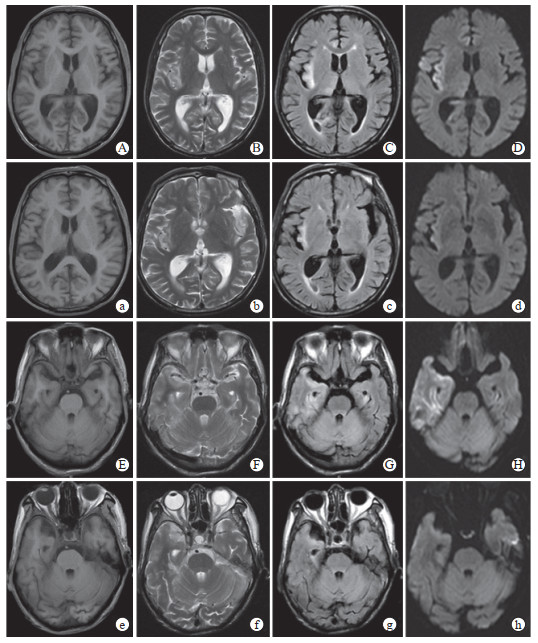

患者入院当天予以更昔洛韦(0.25 g静脉输注, 每12 h 1次)抗病毒、头孢曲松钠和奥硝唑经验性抗感染治疗,辅以控制癫痫、抗氧化、降压降糖、补钾补钠、营养支持等治疗。患者症状进一步加重。2022年9月24日,治疗前头颅MRI检查提示T2加权成像(T2-weighted imaging,T2WI)、液体衰减反转恢复(fluid-attenuated inversion recovery,FLAIR)、弥散加权成像(diffusion-weighted imaging,DWI)序列可见双侧额、颞叶及海马区异常信号(右侧为著)(图 1A~1H),FLAIR序列可见“刀切征”(图 2),磁敏感加权成像(susceptibility-weighted imaging,SWI)可见额叶、颞叶、枕叶及基底节区少量微出血灶(图 3);脑脊液外送检测结果回报:脑脊液HSV-Ⅰ型DNA检测阳性,血清HSV-Ⅰ型抗体IgG(+),巨细胞病毒、EB病毒、细菌及真菌二代测序检测均为阴性,综合分析后该患者HSE诊断明确。

图  2   患者治疗前头颅MRI检查

2022年9月24日,治疗前头颅MRI检查:A、B为冠状位FLAIR序列,可见典型“刀切征”病灶.MRI:磁共振成像;FLAIR:液体衰减反转恢复.

HSE的辅助检查中,头颅MRI诊断HSE的灵敏度高达90%以上,其典型影像学特征包括颞叶中部、眶额叶和岛叶的DWI、T2WI、FLAIR高信号,可累及海马旁回等部位[5-6]。MRI检查时HSE典型征象为“刀切征”[7],即在基底节层面可见病灶累及颞叶、岛叶及外囊区域,不累及豆状核,病灶内部呈刀切样切面,凸面向外。本例患者在发病第7天(2024年9月24日)头颅MRI检查显示病变累及双侧颞叶,双侧呈不对称性,右侧明显,并向额叶、枕叶发展,在基底节层面可见“刀切征”。95%以上的HSE患者脑脊液存在异常,细胞数轻度增多,多为单核细胞和红细胞,80%以上患者脑脊液蛋白轻度升高[8-10]。本例患者脑脊液未见红细胞,白细胞计数为70×106/L,单核细胞为主,提示可能合并其他微生物感染,同时脑脊液内蛋白为771.02 mg/L,明显升高,提示该患者血脑屏障损伤严重,可能合并免疫反应异常。宏基因组二代测序技术可对中枢神经系统感染的病原体做到精准检测,采用该技术检测出脑脊液中HSV-DNA阳性是诊断HSE的重要指标,灵敏度和特异度分别高达98%和94%[11-12]。本例患者检测到脑脊液HSV-DNA阳性,更加支持了HSE的诊断。